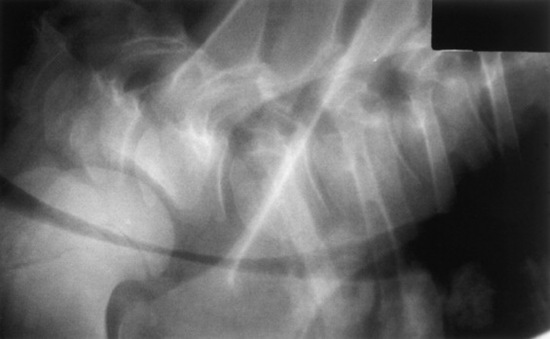

Confirmation requires endoscopy of the ethmoid conchae and skull radiography (Figs. 31-45 and 31-46); however, the origin and extent of the mass can be delineated more accurately by computed tomographic examination of the skull. Sinoscopy may be of diagnostic value in horses with ethmoid hematoma involving the paranasal sinuses without protrusion into the nasal cavity. Rarely, ethmoid hematoma infiltrates the nasal conchae; these lesions, identifiable by CT, may be missed by sinoscopy. Because ethmoid hematoma is bilateral in approximately 30% of affected horses, it is prudent to examine both the left and right ethmoidal conchae. The ethmoidal labyrinth is visible approximately 25 cm from the nares, with the endoscope positioned in the ventral nasal meatus and the viewing tip deflected dorsally. The rostral surface of the ethmoidal concha does not protrude beyond the caudal nasal cavity and has a bulbous shape and a moist pink to pale red mucosal covering.

image

Fig. 31-45 Endoscopic view of left ethmoturbinate. A, Normal appearance. B, Ethmoturbinate obscured by an ethmoid hematoma.

Fig. 31-46 Lateral radiograph demonstrating an ethmoid hematoma.

Beyond the rostral surface the numerous pillars that form the ethmoidal conchae and separate the ethmoidal spaces (cellulae ethmoidales) are visible. Ethmoidal hematomas that project into the ventral meatus or through the choana into the nasopharynx often obscure the ethmoidal concha. Occasionally, unilateral ethmoid hematomas that have expanded into the nasopharynx may protrude into the contralateral ventral meatus, obscuring the view of the ethmoidal labyrinth on that side. The origin of hematomas that expand dorsally into the frontal sinus may not be visible on endoscopy, but hemorrhage that originates deep to the visible portion of the ethmoidal conchae may be evident or may be noticed from the region of the nasomaxillary opening in the middle meatus. Visible ethmoid hematomas can vary in color from deep red to red-purple or may have a yellow-brown or yellow-green-brown to bronze color. The surface is irregularly rounded, with small punctate hemorrhages or erosions, and may be partially covered in yellow-white mucopurulent material that may be admixed with blood. Often the floor of the ventral meatus and the regions of contact with the nasal cavity have pooled exudate of blood and mucopurulent matter. Manipulation of the visible surface of the hematoma with the tip of the endoscope may elicit bleeding or oozing.

Recognition of a discrete, often smooth-surfaced homogeneous radiodensity originating from the ethmoidal conchae and extending into the frontal, maxillary, or sphenopalatine sinuses or into the pharynx or nasal cavity is suggestive of an ethmoid hematoma. Radiography is beneficial in determining the extent of the hematoma and in identifying suspected ethmoid hematomas that are not visible by endoscopy; however, precise definition of the origin of any hematoma is difficult from radiographic projections. Small hematomas contained within the ethmoid labyrinth may not be visible on radiographs. Computed tomographic examination of the skull allows more accurate assessment of the origin of the ethmoid hematoma,1207,1209 allows determination of the extent of involvement of the paranasal sinuses and conchae, and facilitates surgical planning.